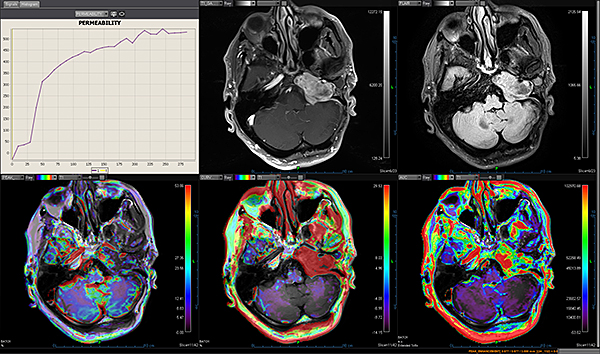

Додаток Brain Tumor Streamlined.

Додаток Brain Tumor пропонує автоматизовану покрокову обробку, включаючи кількісний мультипараметричний аналіз. Ця програма також включає оптимізований алгоритм корекції витоку контрастної речовини для підвищення точності оцінки DSC MР-перфузії.

Додаток MR Neuro

Додаток Neuro інтегрований у розширену візуалізацію Vitrea і забезпечує спеціальні протоколи для пухлини мозку та розширені протоколи інсульту, які забезпечують швидку оцінку захворювань головного мозку.

Обчислює оптимізовані параметричні карти (rBV, rBF, TTP, MTT, TMAX, tMIP) із первинної перфузійної серії

Використовує автоматизований та настроюваний робочий процес

Включає повністю автоматизовану поетапну обробку для пацієнтів з пухлинами мозку, включаючи кількісний та якісний мультипараметричний аналіз

Забезпечує корекцію витоку контрасту та створення карти K2 rBV

Пропонує один спеицифічний додаток: Розширений додаток Brain Tumor DSC DCE Expanded